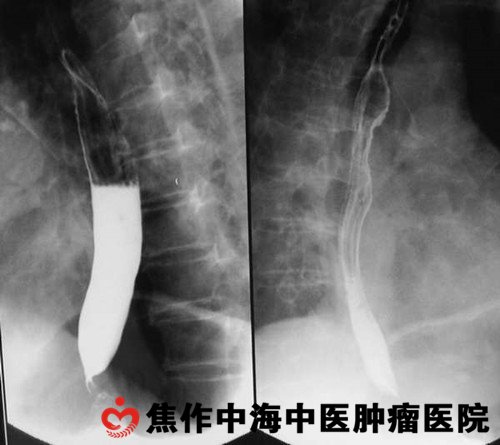

孟拥堂木然地站起身来,轻轻推开诊室的门,小护士见他进来,随手从手边的一摞检查报告单中找出写着孟拥堂名字的报告单。看着检查报告单的结果,即使早就有心理准备的孟拥堂,还是如遭雷击一般呆住了:食管胃交界腺癌,也就是俗称的贲门癌,死亡率和发病率在各类恶性肿瘤中位居前列。

就这样,孟拥堂父子次日来到焦作中海中医肿瘤医院,请张中海大夫为孟拥堂治病。张中海大夫仔细检查了孟拥堂的身体状况后告诉他:不用怕,你现在的身体状况比想象中的好,只要你积极配合治疗,一个疗程二十天, 我有把握让你恢复正常生活。

张中海大夫的话,重新燃起了孟拥堂生的希望。在孟拥堂的积极配合下,经过一个疗程的精心治疗,他便恢复了正常生活。